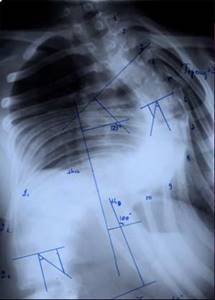

До сих пор в ортопедии принято множество методик измерения угла искривления позвоночника, и, соответственно, множество различных классификаций с разными величинами углов в градусах. Измеряется искривление так: на рентгенограмме надо провести несколько прямых линий между позвонками, а затем измерить углы между ними. В нашей стране наиболее распространена классификация, предложенная В.Д. Чаклиным. В иностранных научных источниках чаще приводится метод Дж. Кобба. Суть его заключается в следующем: на рентгеновском снимке позвоночника врач измеряет S-образное двойное искривление. В верхнем участке искривления с помощью линейки проводят две горизонтальные линии: одна над верхним позвонком, от которого идет кривизна, другая - над нижним. Если провести еще две линии, идущие перпендикулярно первым, образуется угол. Его и измеряют в градусах

Как видно, принцип измерения как у русского, так и американского профессора практически одинаковый. Разница в том, что по Чаклину, чем больше градусов, тем легче степень болезни, а по Коббу - наоборот.

Классификация выраженности сколиоза по В.Д. Чаклину (слева), по Лж. Коббу (справа) Степени тяжести сколиоза (углы искривления позвоночника, в градусах) Графический расчет на рентгенограмме: а - I степень; б - II степень; в - III степень; г - IV степень.

Глава 2.2 Четырехстепенная классификация сколиоза

Первая степень.

Клинически определяется небольшая ассиметрия частей корпуса (надплечий, лопаток), линия остистых отростков слегка искривлена. На выпуклой стороне искривления позвоночника может определяться небольшой мышечный валик. Появляются начальные признаки торсии позвонков. Рентгенологически угол искривления позвоночника до 10°.

Вторая степень.

Ассиметрия частей корпуса становится более выраженной, появляется небольшое отклонение корпуса в сторону. Мышечный валик четко определяется. Рентгенологически отмечается ясная торсия и небольшая клиновидная деформация позвонков. Угол искривления позвоночника

от 10° до 25°.

Третья степень.

Ассиметрия частей корпуса увеличивается. Грудная клетка резко деформирована: сзади на выпуклой стороне дуги искривления позвоночника - задний реберно-позвоночный горб, спереди на вогнутой стороне - менее выраженный передний реберный горб. В поясничном разделе часто усилен лордоз. На рентгенограмме - выраженная торсия и клиновидная деформация позвонков и дисков. Угол искривления позвоночника от 25° до 40°.

Четвертая степень.

Деформация позвоночника и грудной клетки становится грубой и фиксированной. Угол искривления позвоночника более 40°.